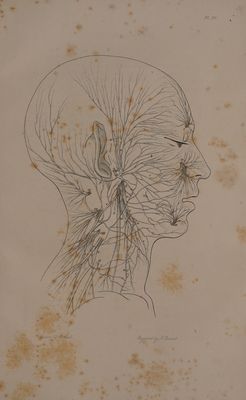

The anatomy and philosophy of expression as connected with the fine arts / By Sir Charles Bell.

- Charles Bell

- 1844

Credit: The anatomy and philosophy of expression as connected with the fine arts / By Sir Charles Bell. Source: Wellcome Collection.